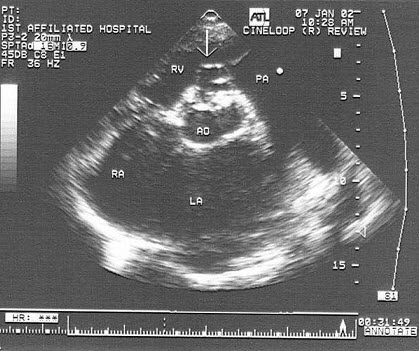

52、填空题

如图,二维超声心动图中,此为____________切面。